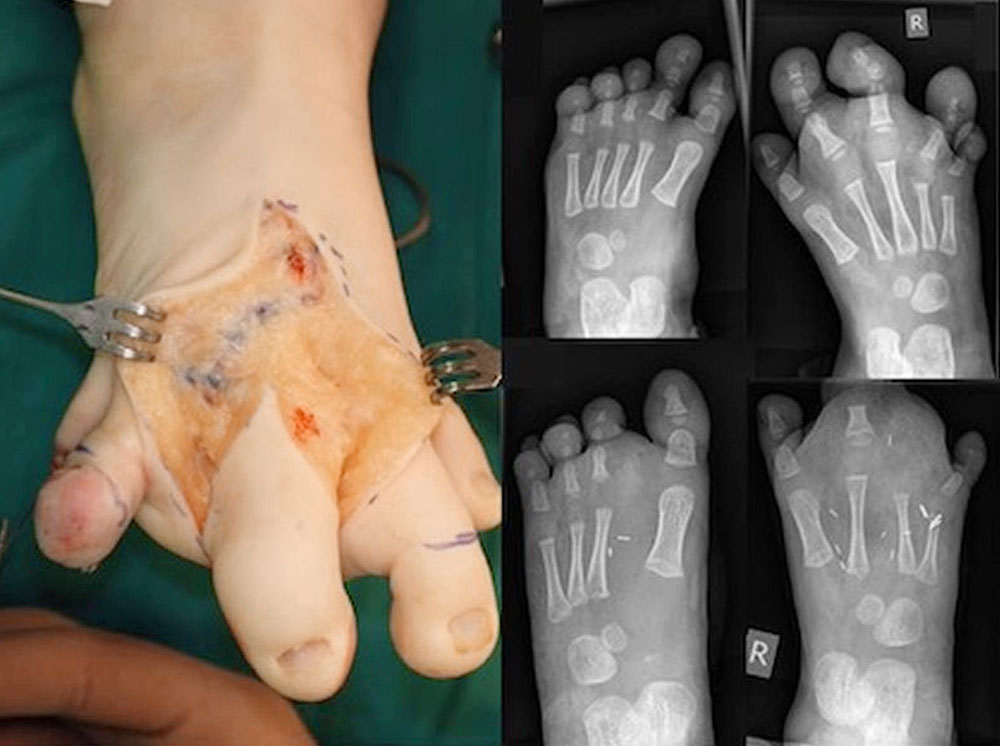

Mixed vascular malformations often occur as capillary lymphatic-venous malformations (CLVM) in the context of circumscribed tissue hyperplasia. Well-known examples are Klippel-Trénaunay syndrome with capillary and venous (+/- lymphatic) malformations and skeletal overgrowth, and CLOVES syndrome (Congenital Lipomatous Overgrowth, Vascular malformations, Epidermal nevi, Skeletal anomalies). The majority of these overgrowth forms affect the lower extremity. The aim of treatment is to make life easier for those affected by ensuring painless feet and enabling them to wear a ready-made standard shoe of the same size as the other foot.

Establishing the indication and performing the surgical resection requires a lot of experience in this situation, especially when looking at the long-term course.

The feet can be surgically narrowed by means of ray resection. Prominent parts are resected if they cause pressure sores. We know from malformation surgery that walking in preschool children is not impaired by resection of one of the middle rays. After resection of the complete ray, the deep metatarsal ligament is reconstructed with 3-0 or 4-0 PDS sutures.

Length overgrowth of the foot can be limited by open or percutaneous epiphysiodesis. The timing of this operation depends on the length of the foot of the same-sex parent. In upright X-rays with a measuring scale, the length of the individual limbs on both sides is measured and compared to the parent. After the age of 10 to 12 years, epiphysiodesis is no longer useful as there is only little residual growth to align for discrepancies.